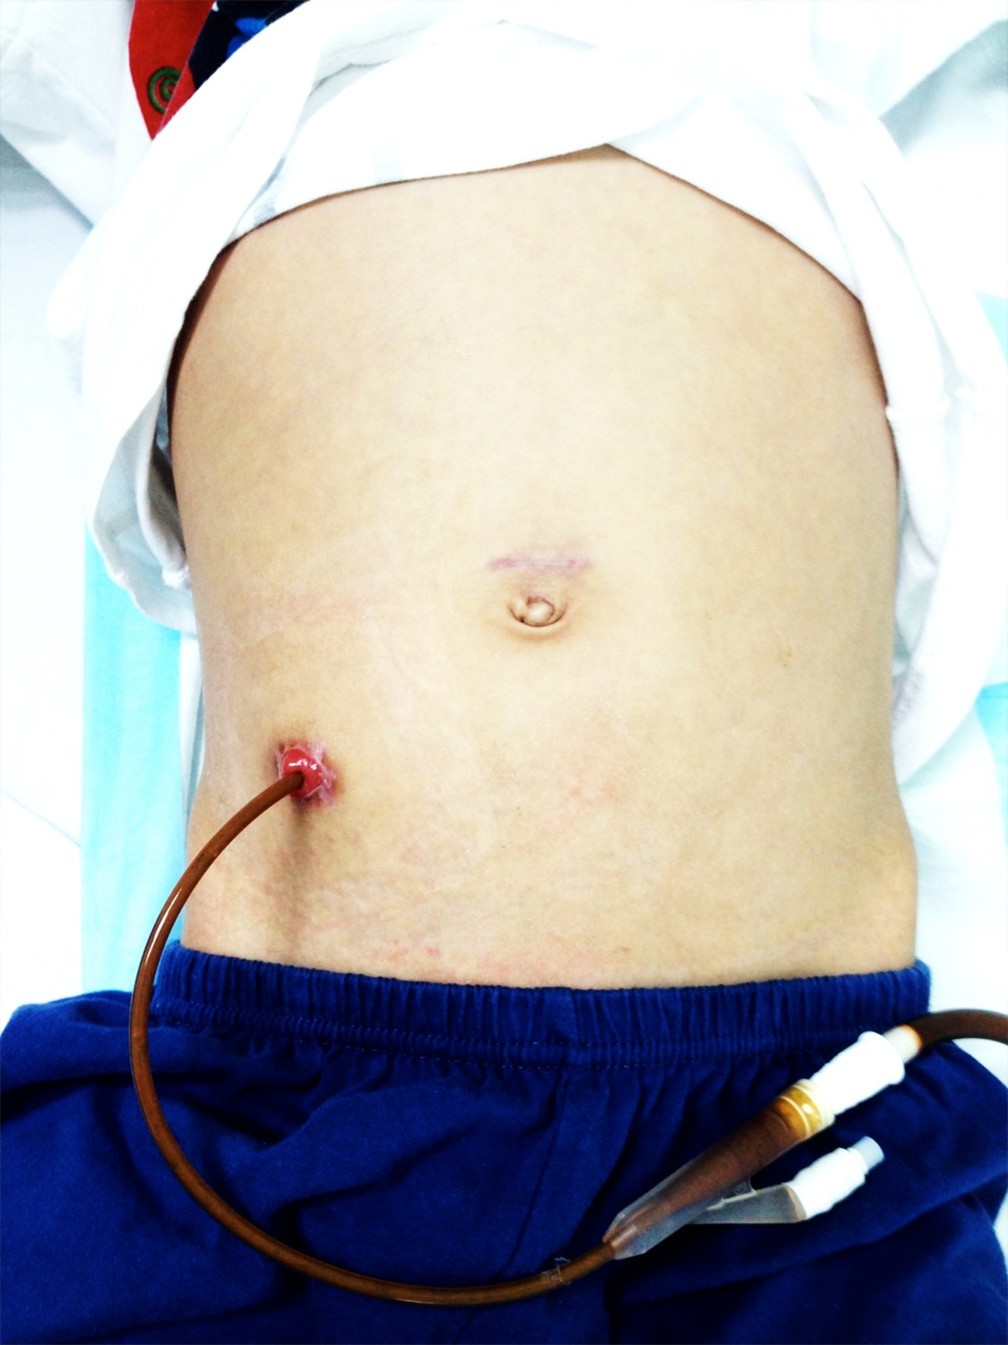

- Antegrade continence enema (ACE, Figure 3): formation of appendix stoma and to administer antegrade enema to flush out faeces

Figure 3: ACE stoma for administration of colonic enema to flush out faeces